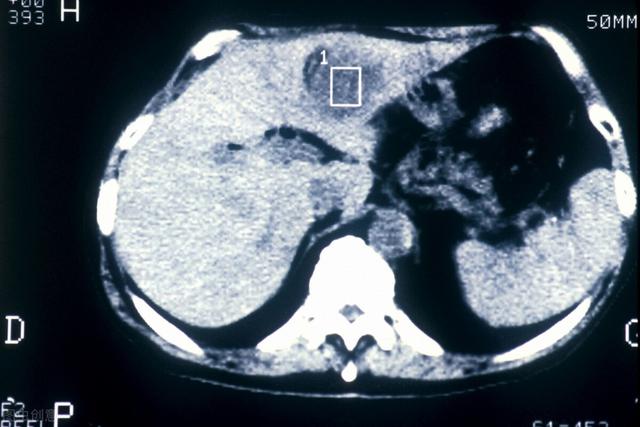

- Si une échographie du foie ne révèle pas de tumeur dans le foie, ou si la nature de la tumeur ne peut être déterminée, une alpha-fœtoprotéine élevée est hautement suspecte de la présence possible d'un carcinome hépatocellulaire.Une tomodensitométrie du foie peut être réalisée.Je recommanderais d'emblée une tomodensitométrie améliorée du foie, car cette technique est relativement efficace pour identifier les tumeurs hépatiques.

(Comme indiqué : cancer du foie métastatique)